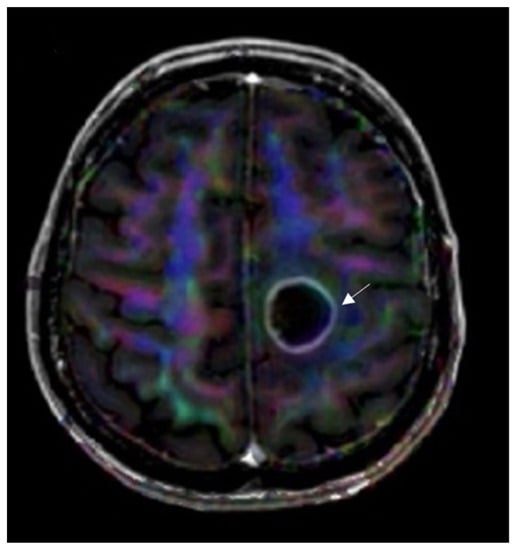

3.4.3. Diffusion Tensor Imaging